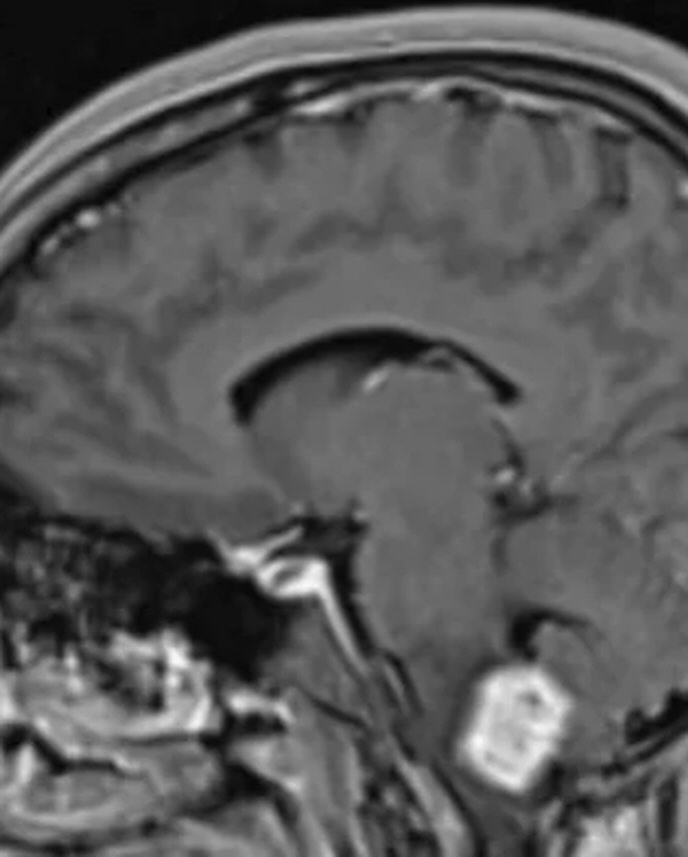

Aunque en diciembre la Justicia ordenó a DOSEP cubrir el 100% de este medicamento mediante una medida cautelar, la obra social aún no cumplió con lo dispuesto. Mientras tanto, la enfermedad ha avanzado, causando severos dolores y afectando múltiples órganos, incluyendo la médula, el cerebelo, el páncreas, el riñón y los pulmones.